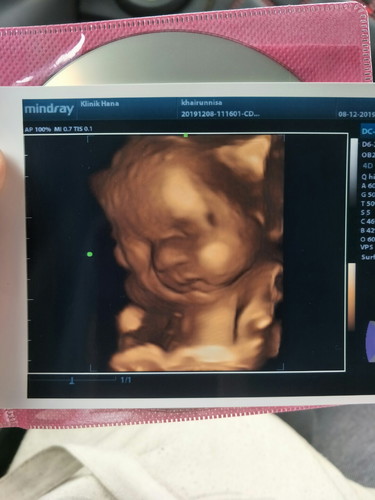

Sbb excited.. Hehehe.. Doakan ye mummy smua.. Skrg 29weeks .. ???

amboii pipii 😍haritu dah scan 5d masa 25w. ni 30w gatal tangan nak scan lagi, rindu nak tengok.

Tengok dlm tu pun dah comei tembam apatah lagi bila keluar nanti mesti comei serupo ibunya jugak 😍

Semoga dipermudahkn..geram tgk pipi baby..tembam..sy isnin ni baru bt details scan

Alalalaaa tembamnya dia. Comel betul 😍 semoga semuanya dipermudahkan mommy 😀

Ya allah comelnyaaaa 😍😍 . Sis biasaa scan 4d bayar berapa ??

Heee tq sis..😍😍 klinik ni saya bayar 100rm, dpt skeping gmba ni dgn cd..

Comelnyaaaaa. Baby girl? Semoga dipermudahkan mommy & baby comel

Heee tq mommy. Baby boy ni in shaa Allah.. Hehehe..